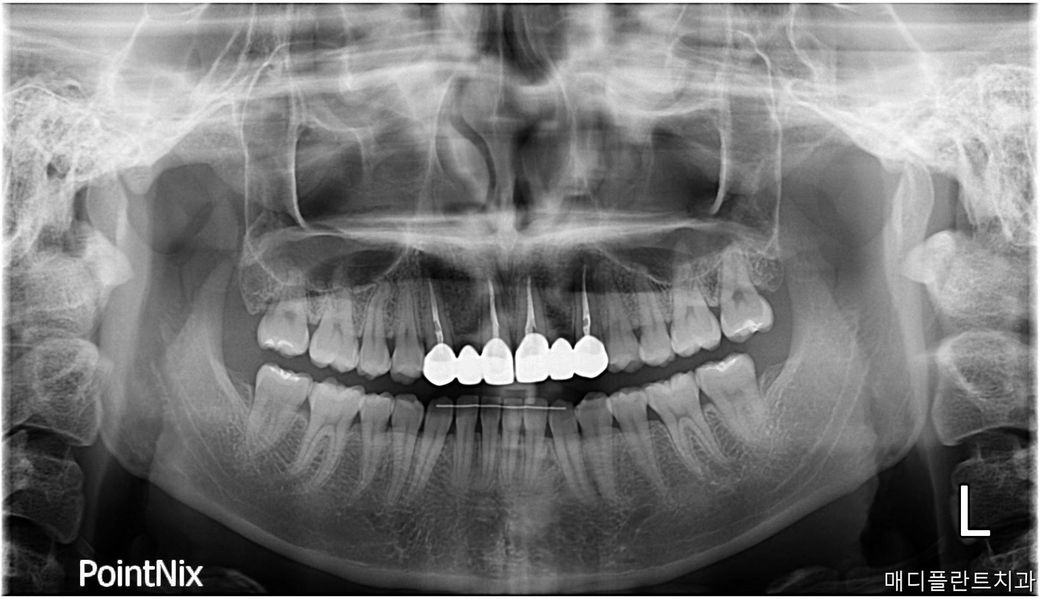

양옆 두번째 앞니가 없어서 송곳니랑 첫번째 앞니 갈아서 10년 전에 브릿지를 했는데요.

스켈링 하러 갔다가 이리저리 사진 찍으시더니 양송곳니 뿌리에 고름이 많이 찼다고 뿌리를 자르고 신경치료를 다시 해야된다고 하시네요. 신경치료를해서 아프진 않습니다.

• 1번 째 사진

사진으로 봤을 경우 치근단에 병소가 보입니다 신경관의 감염으로 인해서 생긴 염증이라면 재신경치료가 필요할수 있습니다.

1. 엑스레이상으로 염증이 보이기 때문에 처치는 필요할 것 같습니다.